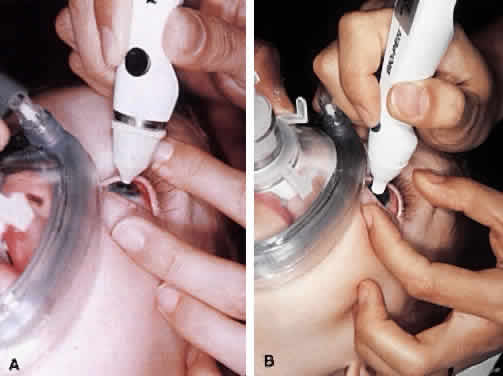

Virtually all of the inhalational anesthetics are known to depress the IOP within minutes of administration.17 Ketamine HCl slowly elevates the IOP as deeper anesthesia is attained.18,19 The benzodiazepines do not appear to have a significant effect on IOP when used in preoperative doses. Midazolam HCl (Versed) is often used as a preoperative sedative in children, and in many cases the child is sufficiently sedated with this medication to perform a quick IOP measurement before the administration of an inhalational general anesthetic. Such a measurement, with the child resting comfortably but not under the influence of the potent inhalational anesthetics, is probably the most accurate. If such a situation cannot be achieved, as in the case of a highly agitated infant or toddler, the anesthesiologist should be aware that it is preferable for the surgeon to measure the IOP as early as possible during the induction of general anesthesia (Fig. 2). At this point in the anesthetic induction, however, airway management is of paramount importance, and the surgeon must defer to the judgment of the anesthesiologist as to when measurements can safely be taken. In most cases, endotracheal intubation is appropriate.

Fundus photography of the optic nerve allows the surgeon to document the extent of progression of the disease (Fig. 4). It is well known that the optic nerve cupping seen in congenital and juvenile glaucoma can to some extent reverse itself,20–22 and this can be used in some cases to gauge the success of therapy. Similarly, axial length measurements by ultrasonic biometry can help establish the degree of disparity between the two eyes, particularly in unilateral cases.23–25 In many cases the disparity decreases after successful therapy,23 and thus a constant or increasing disparity between the two eyes may signal a worsening clinical situation. The Bio-Pen hand-held ultrasonic biometric ruler (see Fig. 2) is a portable device that can be brought to the operating room for intraoperative biometry; because it is similar in size, operation, and appearance to the Tono-Pen, it can also be used in the office setting in young children who have become accustomed to IOP measurements being taken with that device.